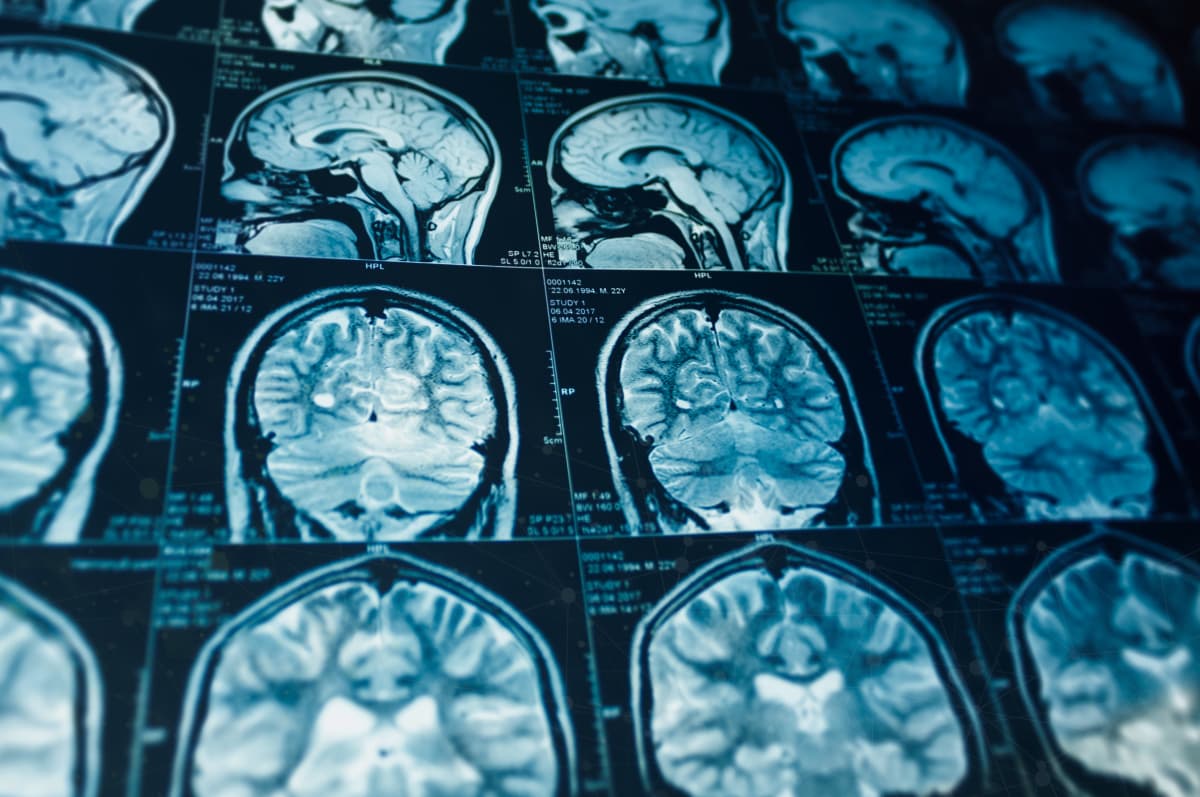

Ata analizuan imazhe të trurit me rezonancë magnetike nga 10,071 fëmijë të moshës 9 dhe 10 vjeç, që banojnë në 17 shtete të SHBA-së.

Nga imazhet u vëzhguan zona të korteksit, shtresa e jashtme e trurit që lidhet me kujtesën, vëmendjen, emocionet dhe gjuhën.

Rezultatet treguan se fëmijët në shtetet më të pabarabarta kishin sipërfaqe më të vogël të korteksit dhe lidhje të ndryshuara midis rajoneve të trurit, pa dallim nëse vinin nga familje të pasura apo të varfra.